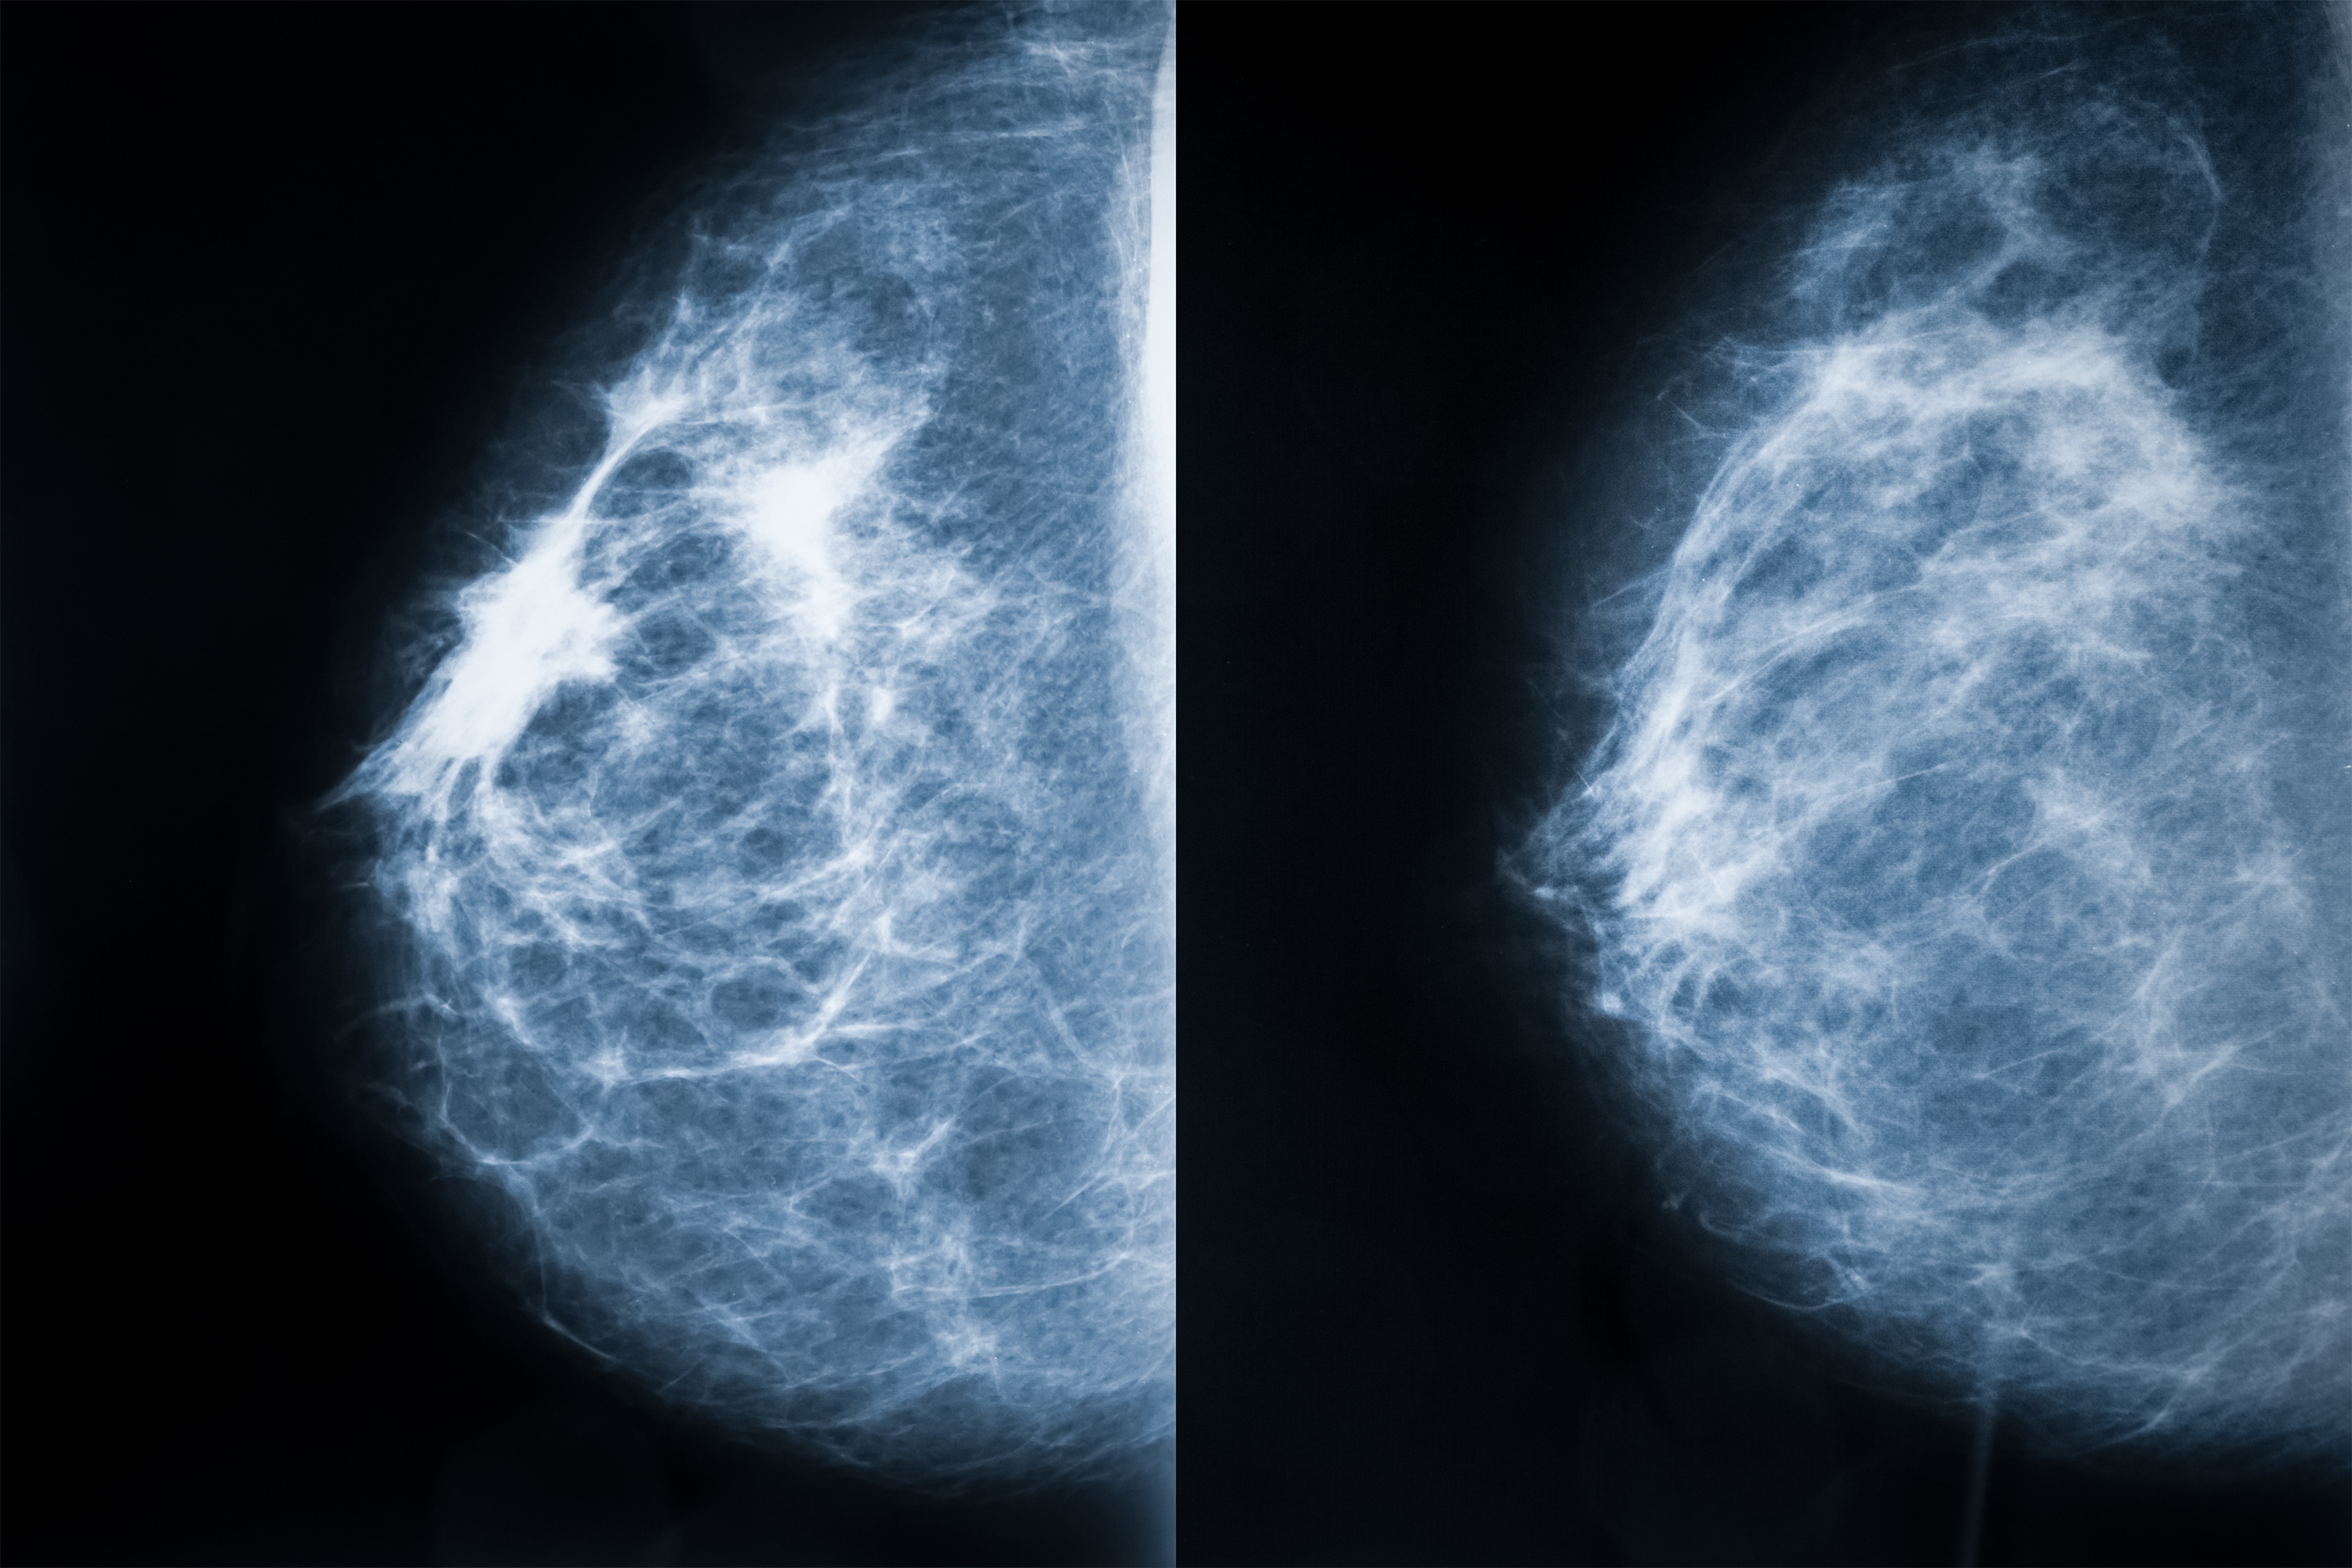

Mammogram X-rays showing breast tissue analysis

Mammography: Standard diagnostic imaging for breast cancer detection and monitoring